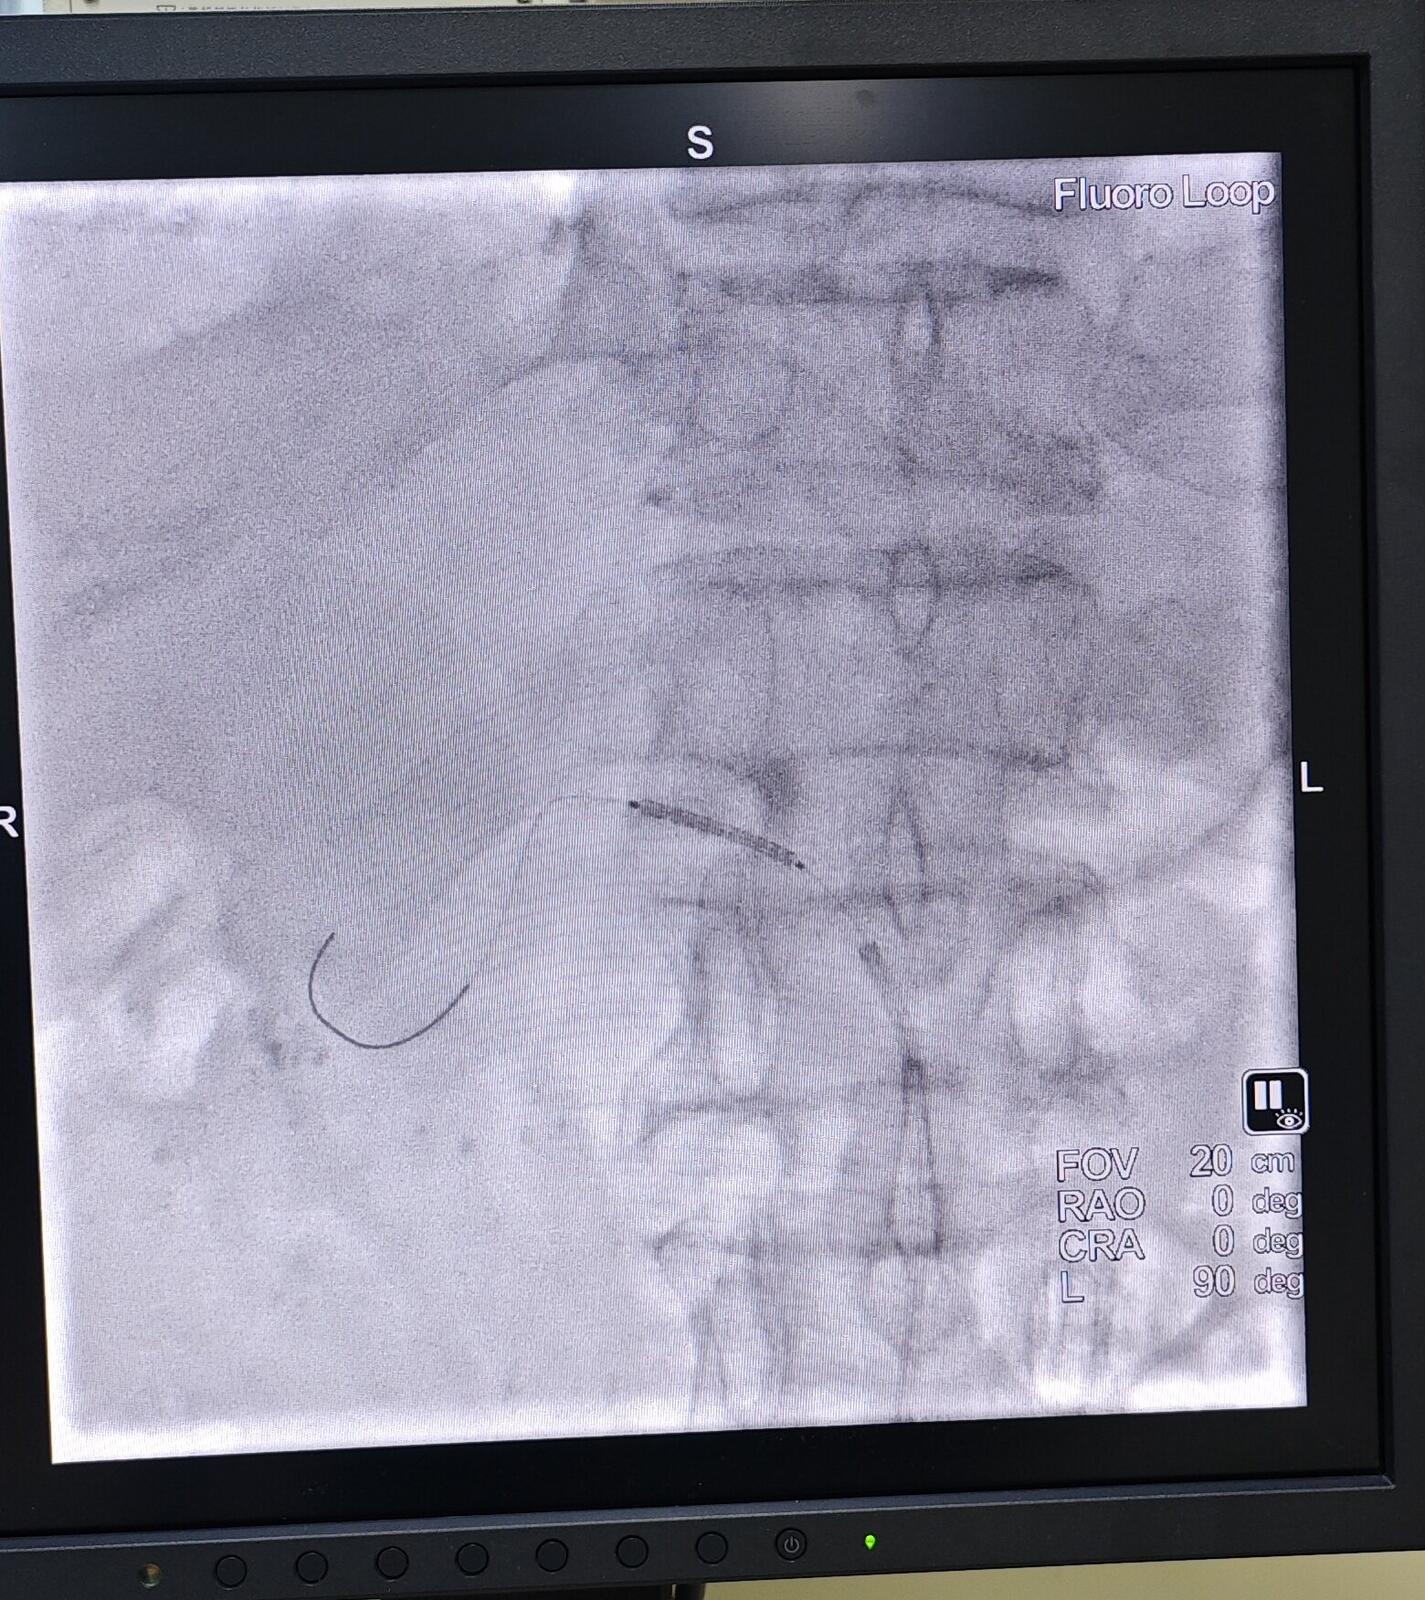

→_→肾动脉介入治疗过程:取仰卧位,常规消毒、铺无菌巾,局麻后穿刺股动脉并置入血管鞘。于患者的第1腰椎处放置猪尾导管行腹主动脉造影明确患者的肾动脉开口以及狭窄的情况。然后通过Cobra导管,进而选择肾动脉造影,从而使狭窄的程度、狭窄的部位、长度以及狭窄段两端正常RA的管腔直径得以明确。利用专用导丝和导管将选好的球囊和支架送到发生病变的位置,球囊扩张后准确释放支架。